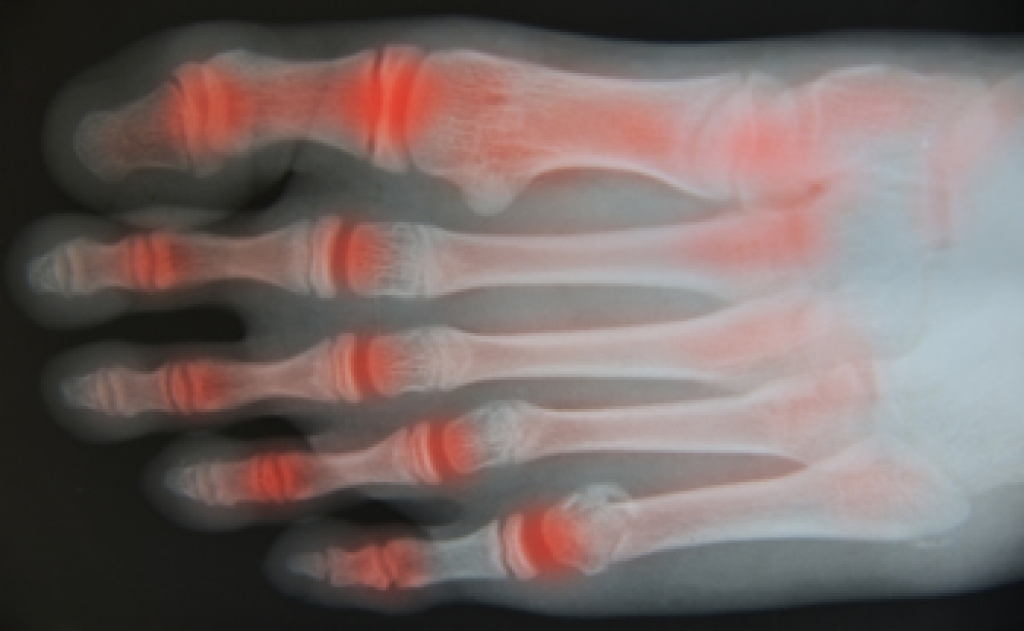

Who Is Most at Risk to Develop Bunions

Bunions, bony protrusions at the big toe joints, can develop due to a variety of factors. While there are lifestyle factors that can contribute, you are more likely to develop bunions if they run in the family, and if you have a certain foot structure. Wearing narrow and ill-fitting shoes increases the chance of bunion formation. Other risk factors for bunions include foot injuries, deformities, activities that place repetitive stress on the feet, or conditions such as arthritis. You can take preventive measures against bunion formation, such as wearing comfortable shoes with adequate toe space and low heels. However, if you already have bunions, they cannot be reversed except through surgery. If you are experiencing pain from bunions, or if you want to address potential risks, it is suggested you consult with a podiatrist who can guide you toward an appropriate treatment plan.

Bunions, bony protrusions at the big toe joints, can develop due to a variety of factors. While there are lifestyle factors that can contribute, you are more likely to develop bunions if they run in the family, and if you have a certain foot structure. Wearing narrow and ill-fitting shoes increases the chance of bunion formation. Other risk factors for bunions include foot injuries, deformities, activities that place repetitive stress on the feet, or conditions such as arthritis. You can take preventive measures against bunion formation, such as wearing comfortable shoes with adequate toe space and low heels. However, if you already have bunions, they cannot be reversed except through surgery. If you are experiencing pain from bunions, or if you want to address potential risks, it is suggested you consult with a podiatrist who can guide you toward an appropriate treatment plan.

If you are suffering from bunion pain, contact Pasquale Cancelliere, DPM of Candria Foot and Ankle Specialists. Our doctor can provide the care you need to keep you pain-free and on your feet.

What Is a Bunion?

Bunions are painful bony bumps that usually develop on the inside of the foot at the joint of the big toe. As the deformity increases over time, it may become painful to walk and wear shoes. Women are more likely to exacerbate existing bunions since they often wear tight, narrow shoes that shift their toes together. Bunion pain can be relieved by wearing wider shoes with enough room for the toes.

Causes

- Genetics – some people inherit feet that are more prone to bunion development

- Inflammatory Conditions - rheumatoid arthritis and polio may cause bunion development

Symptoms

- Redness and inflammation

- Pain and tenderness

- Callus or corns on the bump

- Restricted motion in the big toe

In order to diagnose your bunion, your podiatrist may ask about your medical history, symptoms, and general health. Your doctor might also order an x-ray to take a closer look at your feet. Nonsurgical treatment options include orthotics, padding, icing, changes in footwear, and medication. If nonsurgical treatments don’t alleviate your bunion pain, surgery may be necessary.